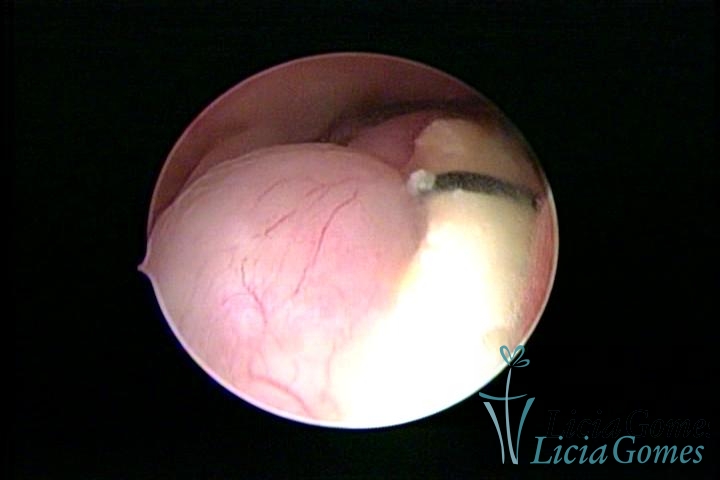

Uterine cavity with IUD